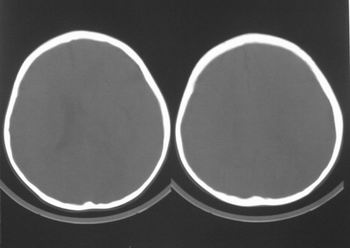

患儿,男,8岁,外伤2小时,无恶心、呕吐,四肢活动正常。既往无任何不适,智力发育正常。

典型的左中颅窝蛛网膜囊肿。

典型的左中颅窝蛛网膜囊肿。最常见的发病部位,张力比较高,相应颅板受压变薄。赶紧治疗,脑组织的功能可能部分恢复。